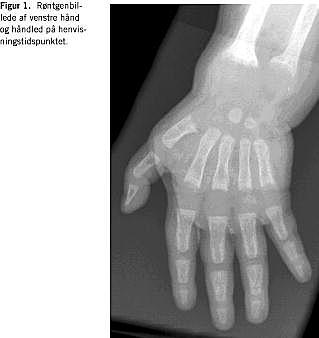

Objektivt fremtrådte barnet psykisk alderssvarende, men den grov- og finmotoriske udvikling var forsinket. Der bemærkedes åbentstående forreste fontanelle, rosenkrans og epifysesvulst ved håndled og knæ. Blodprøverne viste S-calcium-ion 0,83 mmol/l (1,22-1,37) og total S-calcium 1,61 mmol/l (2,17-2,66), S-fosfat 1,12 mmol/l (1,36-2,55) og S-basisk fosfatase 8882 U/l (250-1.000). Der suppleredes med S-parathyroideahormon (PTH) på 86,3 pmol/l (1,1-6,9) og P-25-hydroxy-D-vitamin 84 nmol/l (45-150). Ved en røntgenundersøgelse afsløredes udtalte rakitisforandringer med halisterese og breddeøgede metafyser i hånd- og knæled (Figur 1).